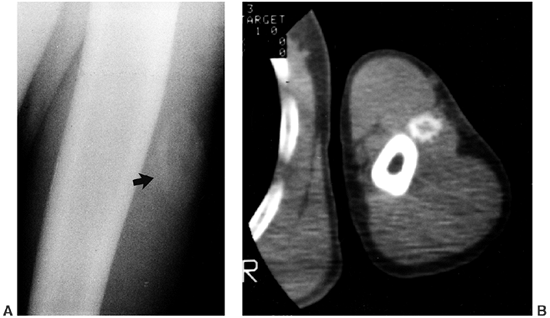

films, which show the abnormalities in most cases of deep VMs,

including phleboliths and enlargement or distortion of soft-tissue

planes (1,16).

Ultrasound and computerized tomography (CT) scans with intravenous

contrast demonstrate similar findings but do not add significant new

information to that shown by plain films. They may be used for

directing aspiration or needle biopsy if a limited specimen is useful.

MRI and magnetic resonance angiography add significant anatomic detail

and are the most informative diagnostic modalities (8).